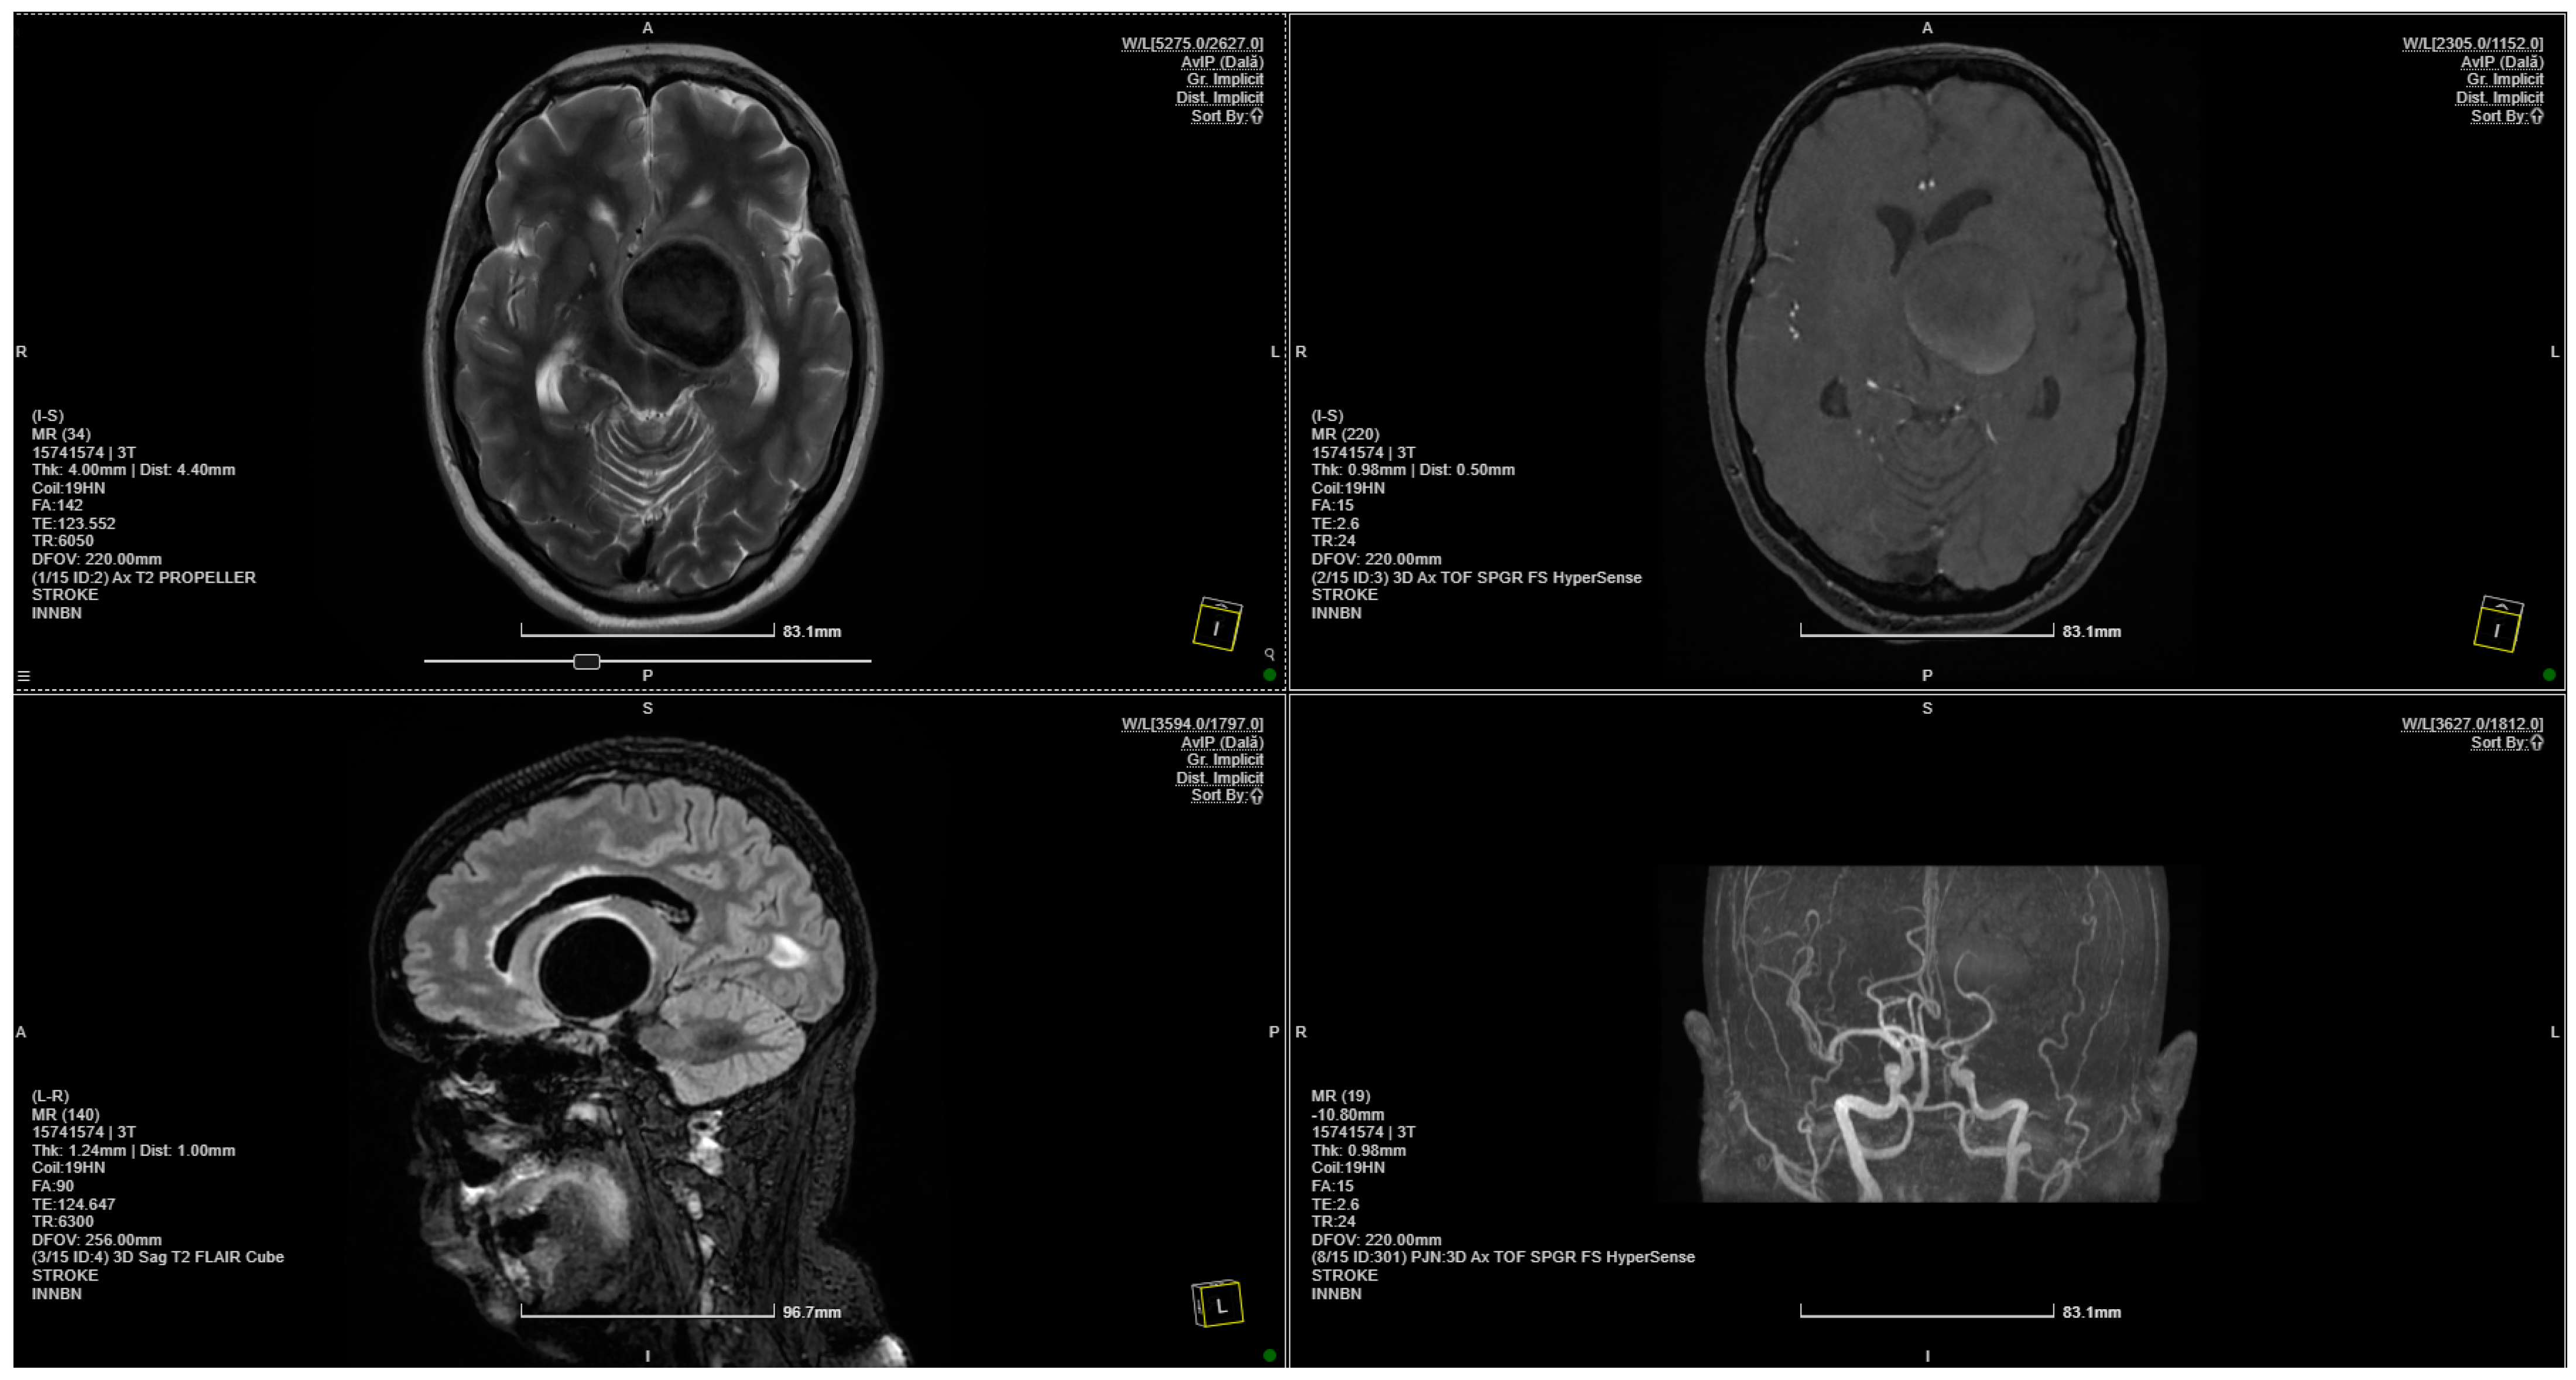

Coanda Effect Displayed in a Giant Intracranial Aneurysm